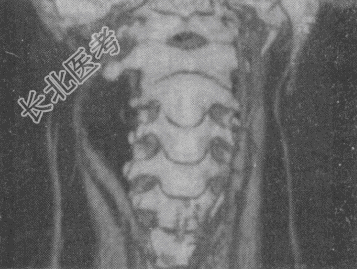

- 单项选择题男,41岁, 右侧咽部不适2年余,有异物感, 声音嘶哑,CT如图, 最可能的诊断是

A、颈动脉体瘤

B、咽旁转移瘤

C、咽旁淋巴瘤

D、小唾液腺瘤

E、咽旁神经鞘膜瘤